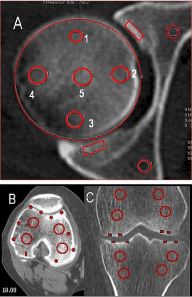

Typical feature of bony density quantitative change in patients with OA is a general density decreasing of femoral and tibial condyles and significant bone induration at subchondral zone, which cannot be treated as sclerotic because bone density at this area is no more than 400-600 HU, while at sclerotic zones the bone density is 1600-2000 HU and more. Bone density at subchondral femoral and tibial condyles is lower in comparison with age normal in all patients with OA, except patients with significant Varus or valgus knee joint deformity (point 5, Figure 4).

Figure 4. MSCT knee-joint. OA. MIP (A). The density was measured at point 5; MPR, Colormap (B). The density was measured at points 3 and 4.